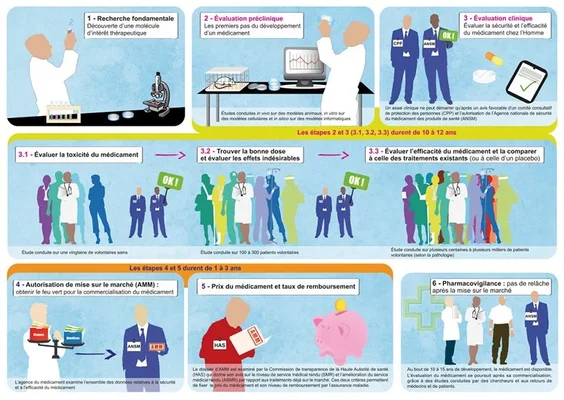

Le passage à l'essai humain représente le Rubicon de toute recherche médicale. Pour le médicament de repousse dentaire, ce protocole est conçu avec une prudence militaire, la sécurité étant le maître-mot absolu à ce stade précoce. L'étude clinique de Phase I a débuté récemment, avec des fenêtres temporelles situées entre juillet et septembre 2024 selon les sources. Ce décalage s'explique par les procédures administratives et logistiques inhérentes aux essais médicaux. L'objectif de cette phase n'est pas encore de prouver l'efficacité esthétique, mais de confirmer que le médicament ne présente pas de toxicité dangereuse pour l'organisme humain.

Le design de cet essai est extrêmement encadré pour maximiser la pertinence des données recueillies tout en minimisant les risques pour les participants. Les données cliniques réelles restent confidentielles pour le moment, protégées par le secret industriel et médical en attendant les premières publications ou communications officielles. Cette confidentialité est habituelle dans les essais précoces, évitant toute spéculation prématurée qui pourrait influencer les résultats ou créer de faux espoirs chez le public. Cependant, la structure même de cet essai nous renseigne sur la stratégie des chercheurs pour les années à venir.

Comment se déroule la Phase I à l'hôpital Kitano ?

Le protocole actuel se déroule principalement à l'hôpital Kitano d'Osaka, le fief du Dr Takahashi. Il implique un groupe restreint de 30 hommes âgés de 30 à 64 ans. Le choix de ne sélectionner que des hommes pour cette première phase vise à éliminer les variables hormonales féminines qui pourraient complexifier l'analyse des effets secondaires. Un critère de sélection crucial est que chaque participant doit manquer d'au moins une dent postérieure. Cette exigence permet de disposer d'un site de mesure clair pour observer une éventuelle repousse, sans attendre des années qu'une dent tombe naturellement.

La durée de l'essai est fixée à onze mois, une période jugée suffisante pour observer la tolérance immédiate et les premiers signes d'activité biologique. Les chercheurs surveilleront de près la réponse de l'organisme à l'administration intraveineuse de TRG035, en analysant le sang et les tissus gingivaux. Si cette première phase confirme l'innocuité du produit, elle ouvrira la porte à des phases plus vastes. La prudence est de mise : même si les résultats sur le furet étaient excellents, le corps humain peut réagir de manière imprévisible, ce qui justifie cette approche progressive par paliers de sécurité.

Qui seront les prochains patients après les adultes ?

Si la Phase I chez l'adulte est concluante, la stratégie de Toregem BioPharma prévoit une transition rapide vers une population pédiatrique. La prochaine étape ciblera les enfants âgés de 2 à 7 ans souffrant d'anodontie congénitale, une condition rare et dévastatrice où les enfants naissent avec peu ou pas de dents du tout. Pour ces patients, l'enjeu est vital : sans dents, l'apprentissage de la mastication et le développement de la parole sont gravement compromis, ainsi que la structure de la mâchoire. Faire repousser des dents naturelles chez ces enfants serait une victoire médicale et humaine inestimable.

À plus long terme, l'ambition est d'élargir l'indication au grand public. L'objectif final est que le médicament puisse être administré à toute personne ayant perdu une dent, que ce soit à cause d'une carie, d'un traumatisme ou d'une maladie parodontale. Le Dr Takahashi envisage un futur où l'on pourrait simplement se faire une piqûre après une extraction pour voir la dent repousser naturellement. Selon le calendrier actuel, si les essais se déroulent sans accroc, la mise sur le marché commercial est visée pour l'année 2030. Cela nous laisse encore quelques années de patience avant de voir ce traitement arriver dans les cabinets français.